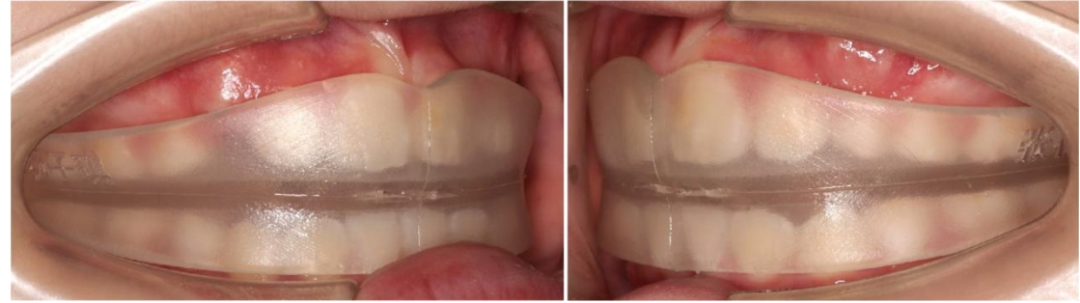

对于乳牙列到替牙前期的孩子,可能会用到硅胶牙套,正如我说每种牙套的制作的方法,是不一样的。

最简单的一种,是不管这人是白种人还是黄种人,都拿一个标准的模型,来做出这样的牙套来,一个标准的牙齿的位置,标准的咬合关系,这是一个典型的预成。就像我穿衣服一样,给我来一个均码的衣服,这个衣服只不过是弹性大,什么人都可以穿。

那还有一种稍微做了一些改变,按照牙弓的宽度做一些挑选,无非就是把样本多增加了几个号,但是这些号我觉得还不够个性化。

因为真正决定着颌骨的发育,可不是单纯的宽度和长度,它至少是需要四个数据,上牙的转矩的角度、覆合覆盖的关系、后部的咬合平面、还有牙弓的宽度,满足这些要素才能真正的称之为三维个性化设计硅胶牙套。

那我们目前使用的Grace个性化矫治器,可以根据孩子的骨骼生长型,来决定后牙的垂直高度,根据孩子的面型来决定他的宽度,根据孩子的嘴型来决定转矩的位置和前牙覆合覆盖的关系,引导骨骼和牙齿的生长。